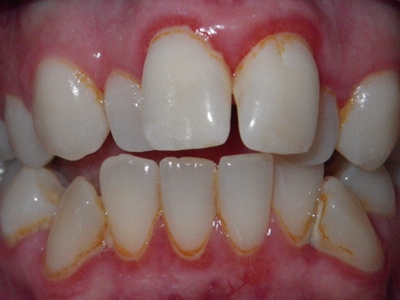

阻生牙是指由于邻牙、骨或软组织的阻碍而只能部分萌出或完全不能萌出,且以后也不能萌出的牙。引起牙阻生的成因,主要是由于颌骨缺乏足够的空间容纳全部恒牙。常见的阻生牙为下颌第三磨牙、上颌第三磨牙及上颌尖牙。

阻生牙可反复引起冠周炎,或引起邻牙牙根吸收和破坏,位置不正,不能完全萌出,好发部位是上、下颌第三磨牙。